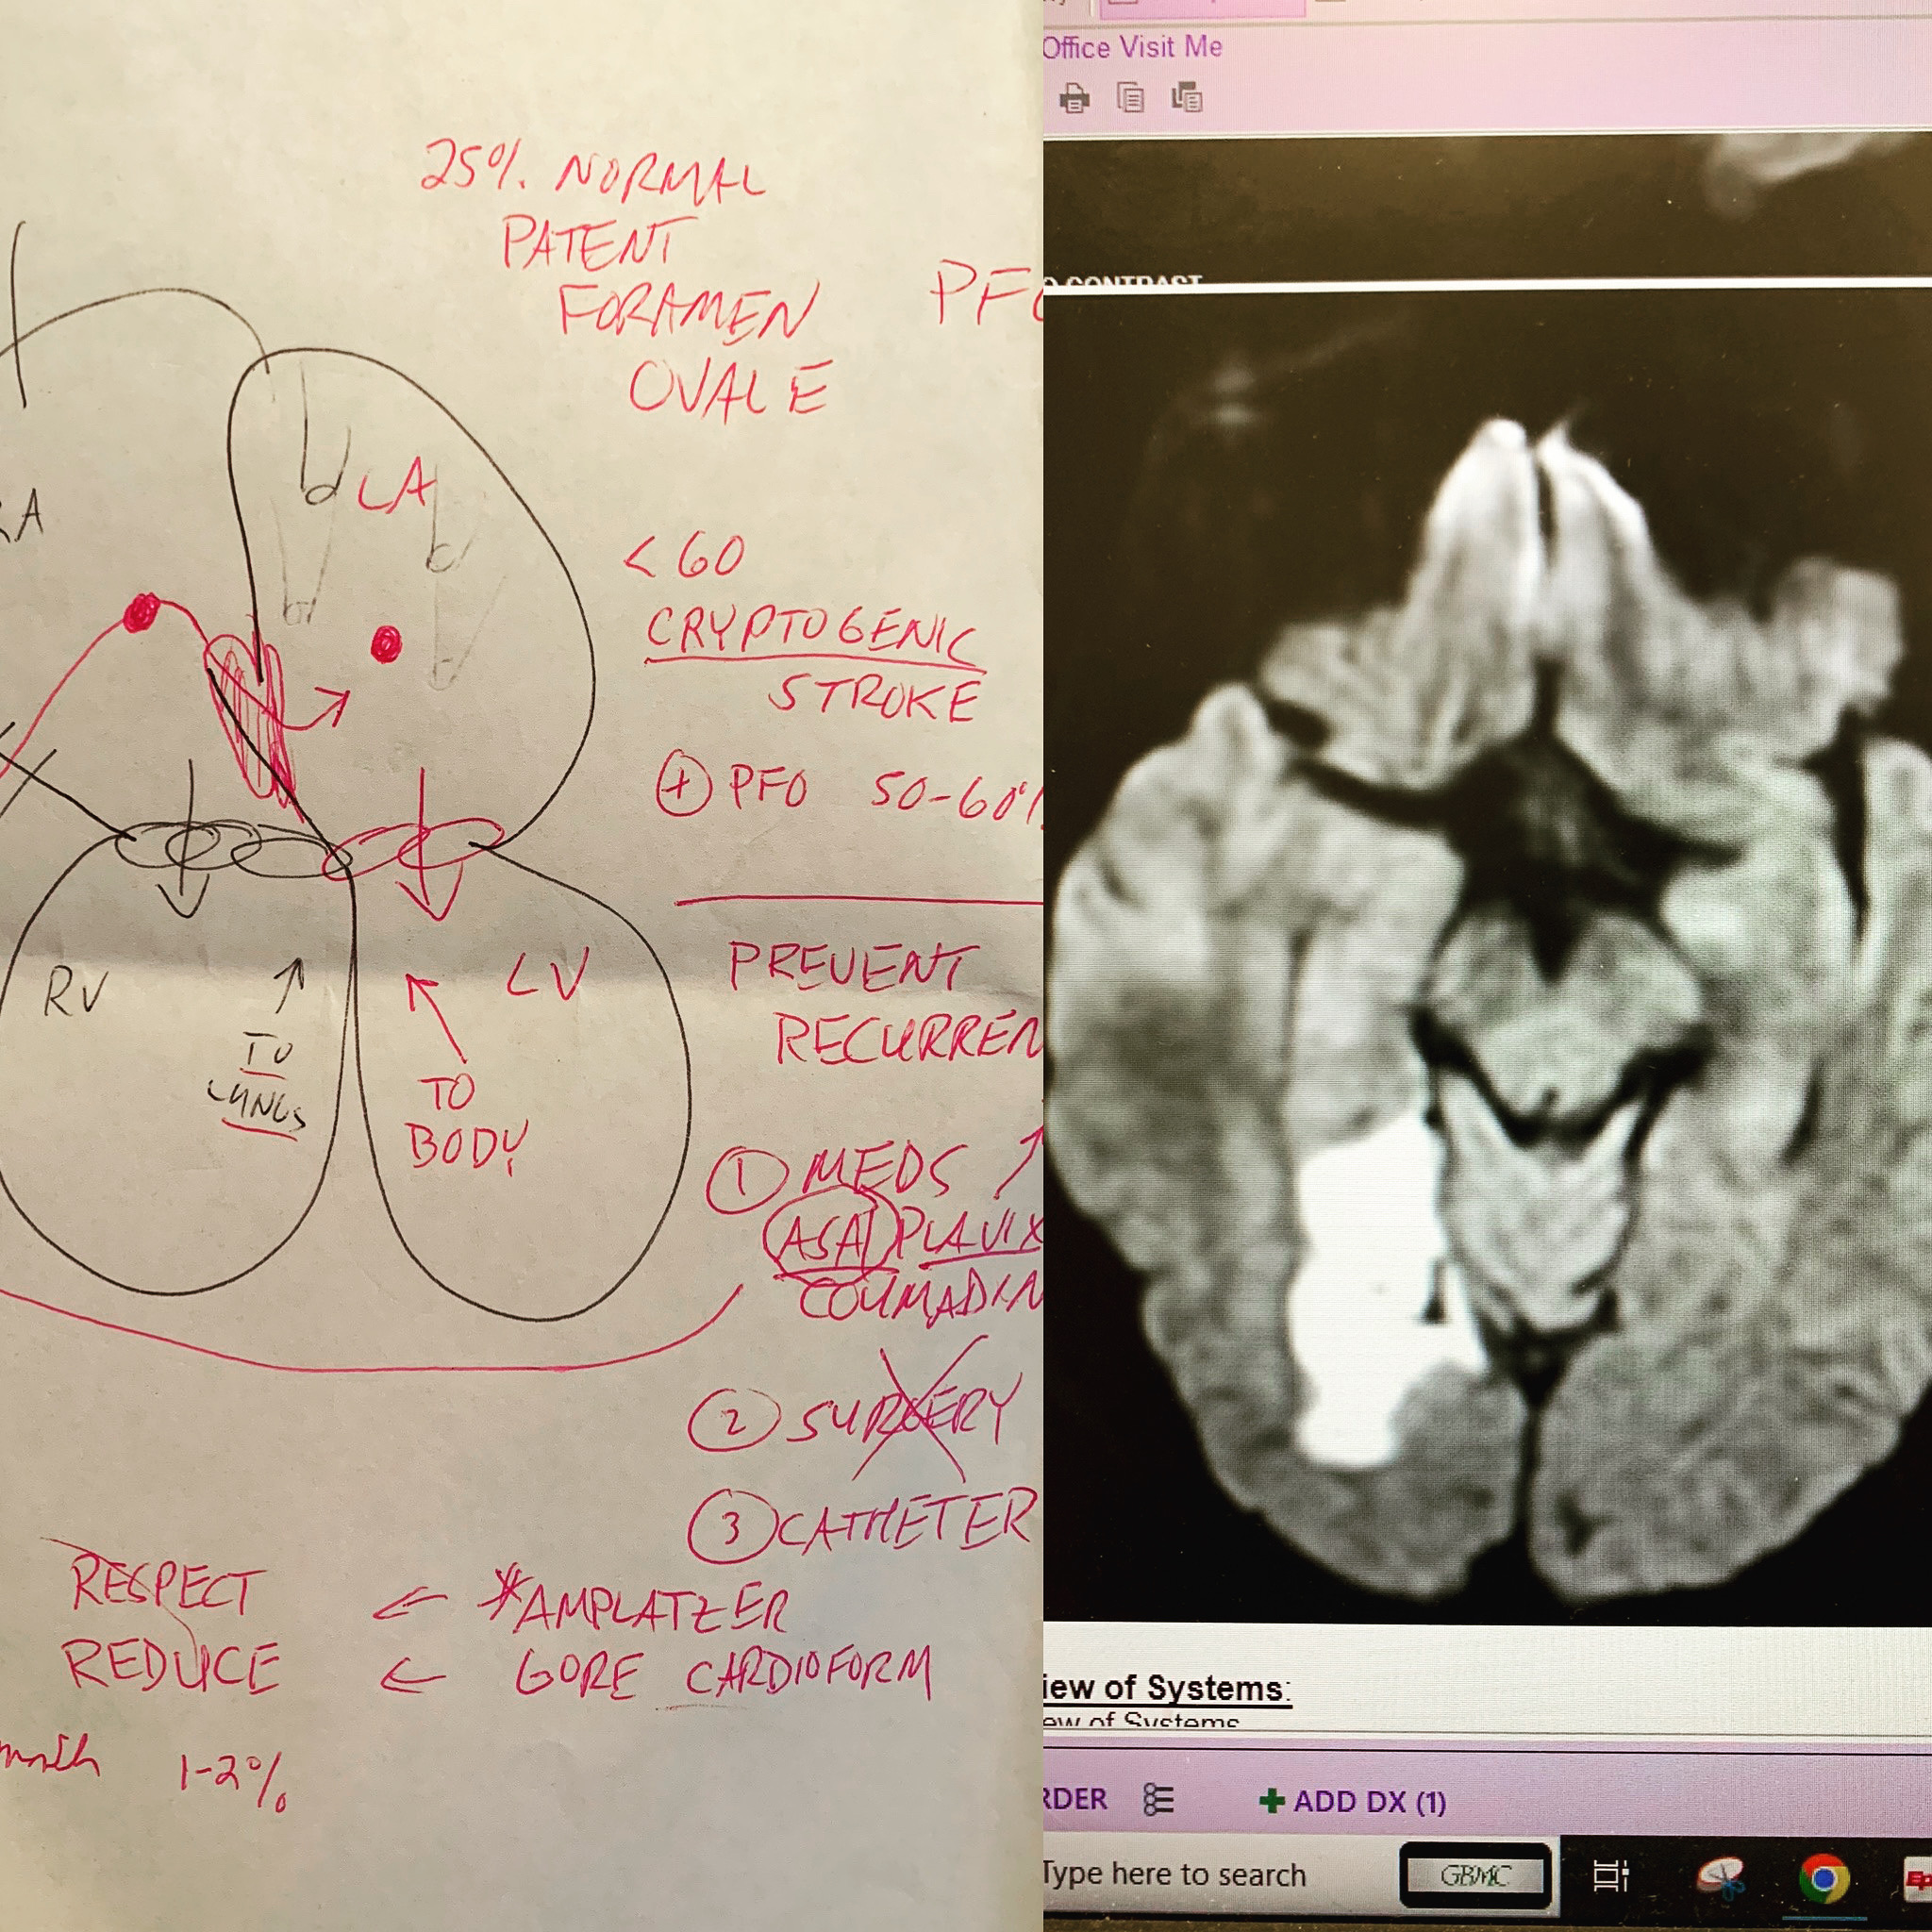

A doctors drawing of a Patent foramen ovale (PFO), and an image of my brain after the stroke

When I had a stroke in September of 2022, I was a healthy 42 year old. What started as general fatigue turned more serious when I lost peripheral vision in my left eye, and had trouble thinking clearly. My vision gradually returned, but smaller ischemic events prompted more tests, which led me to getting a PFO closure in August of 2023.

A PFO (Patent foramen ovale) is a hole between the left and right atria (upper chambers) of the heart. This hole exists in everyone before birth, but most often closes shortly after being born. When someone has a cryptogenic stroke and still has a PFO as an adult, there is thought to be a correlation between the two.